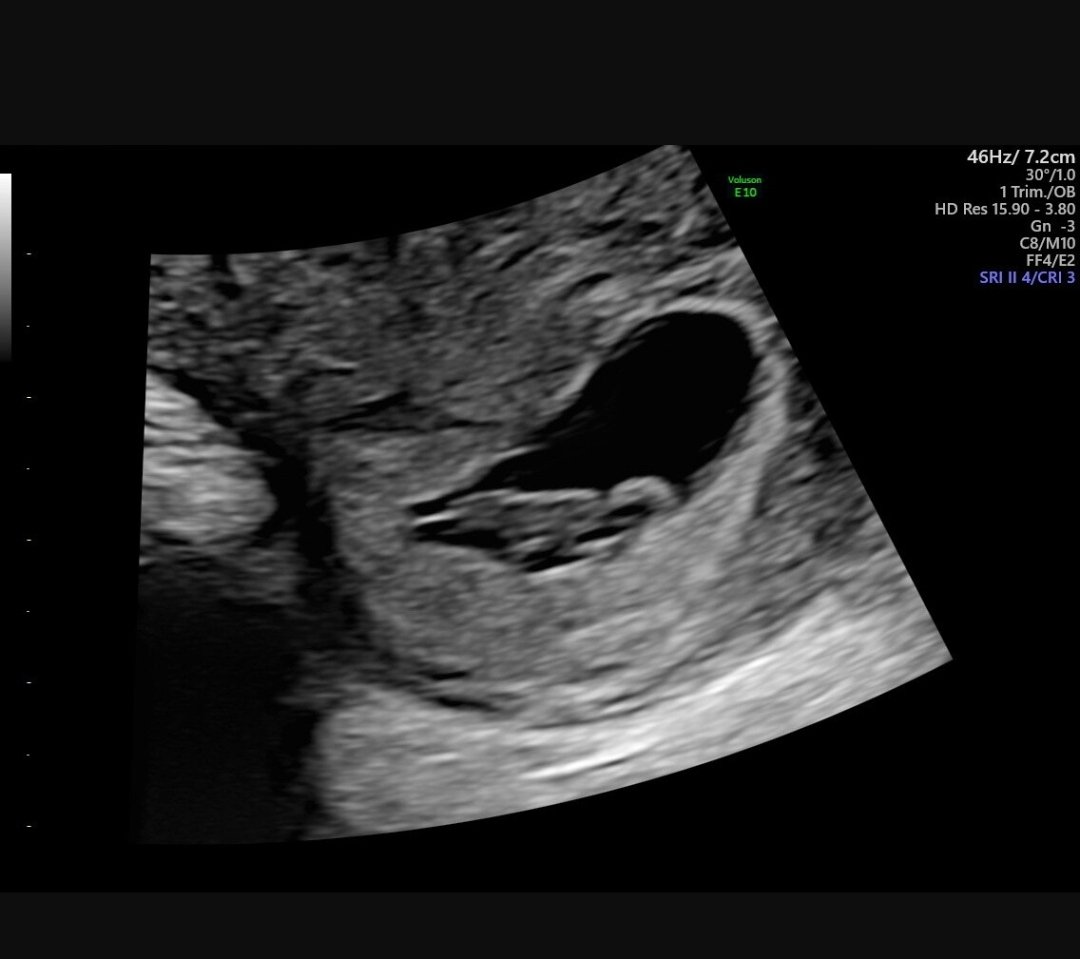

Har noe mensmurringer som gjør meg litt nervøs, men vet også det er normalt med murringer og stikkinger tidlig i svangerskap. Har uansett ringt gyn i dag og fortalt at jeg er gravid, så nå venter jeg på å bli satt opp til time i uke 7 for ultralyd. Er det noen som har erfaring med så tidlig ultralyd og vet hva jeg kan forvente?

Jeg var på det i fjor sommer pga blødninger. Da var det innvendig ul og de fant ingen svar. (Måtte på riksen etter vanlig tul og først der fant de svar pga utstyr og kompetanse).

Skal også.på ul i uke 7 nå pga historikk med forrige svangerskap, og det blir nok innvendig ul da også.

Begge svangerskapene mine har jeg hatt innvendig ultralyd og sett hjerteslag i uke 7. Masse lykke til ❤️ heldigvis går dette stort sett bra!

Jeg var 7+4 og tok utvendig ul. Fikk se en "reke" med hjerteslag :laughing002 :Heartpink

Jeg hadde time i uke 6 selv pga jeg skulle starte opp med noe hjelpemedisiner, og alt jeg så da var egentlig en ert som banket. Hele embryoet er jo bare et hjerte omtrent på starten :hilarious: Men det er jo akkurat det man ønsker å vite på det tidspunktet- banker hjertet og eventuelt i riktig frekvens?

Jeg tok ultralyd 6+4 i forrige svangerskap, så da at hjertet slo og alt var som det skulle. Håper det går bra for deg!